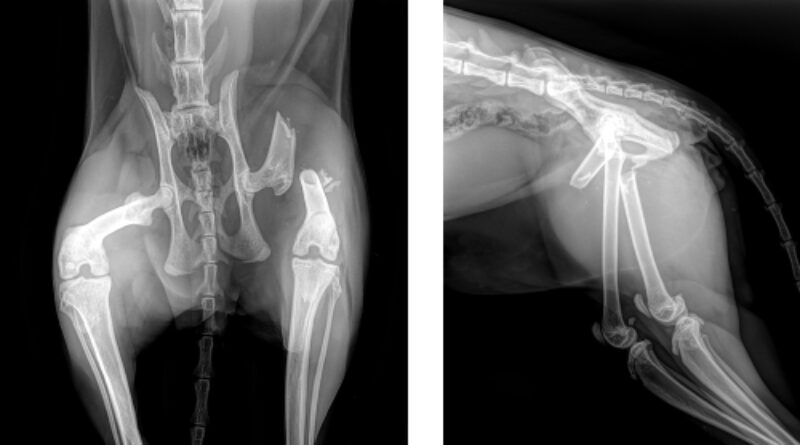

Röntgen

Es gab keine sichtbaren Schäden der Knöchernen Strukturen der Vordergliedmaße. Es bestand eine distale Fraktur des Femur, das Becken war intakt. Verdachtsdiagnosen: Stumpfes Trauma am Kopf, Leichte Gehirnerschütterung. Plexusabriss (Plexus brachialis Läsion, vermutlich axillar) vorne rechts. Geschlossene, stark verschobene Querfraktur / Trümmerfraktur des linken Femurs.